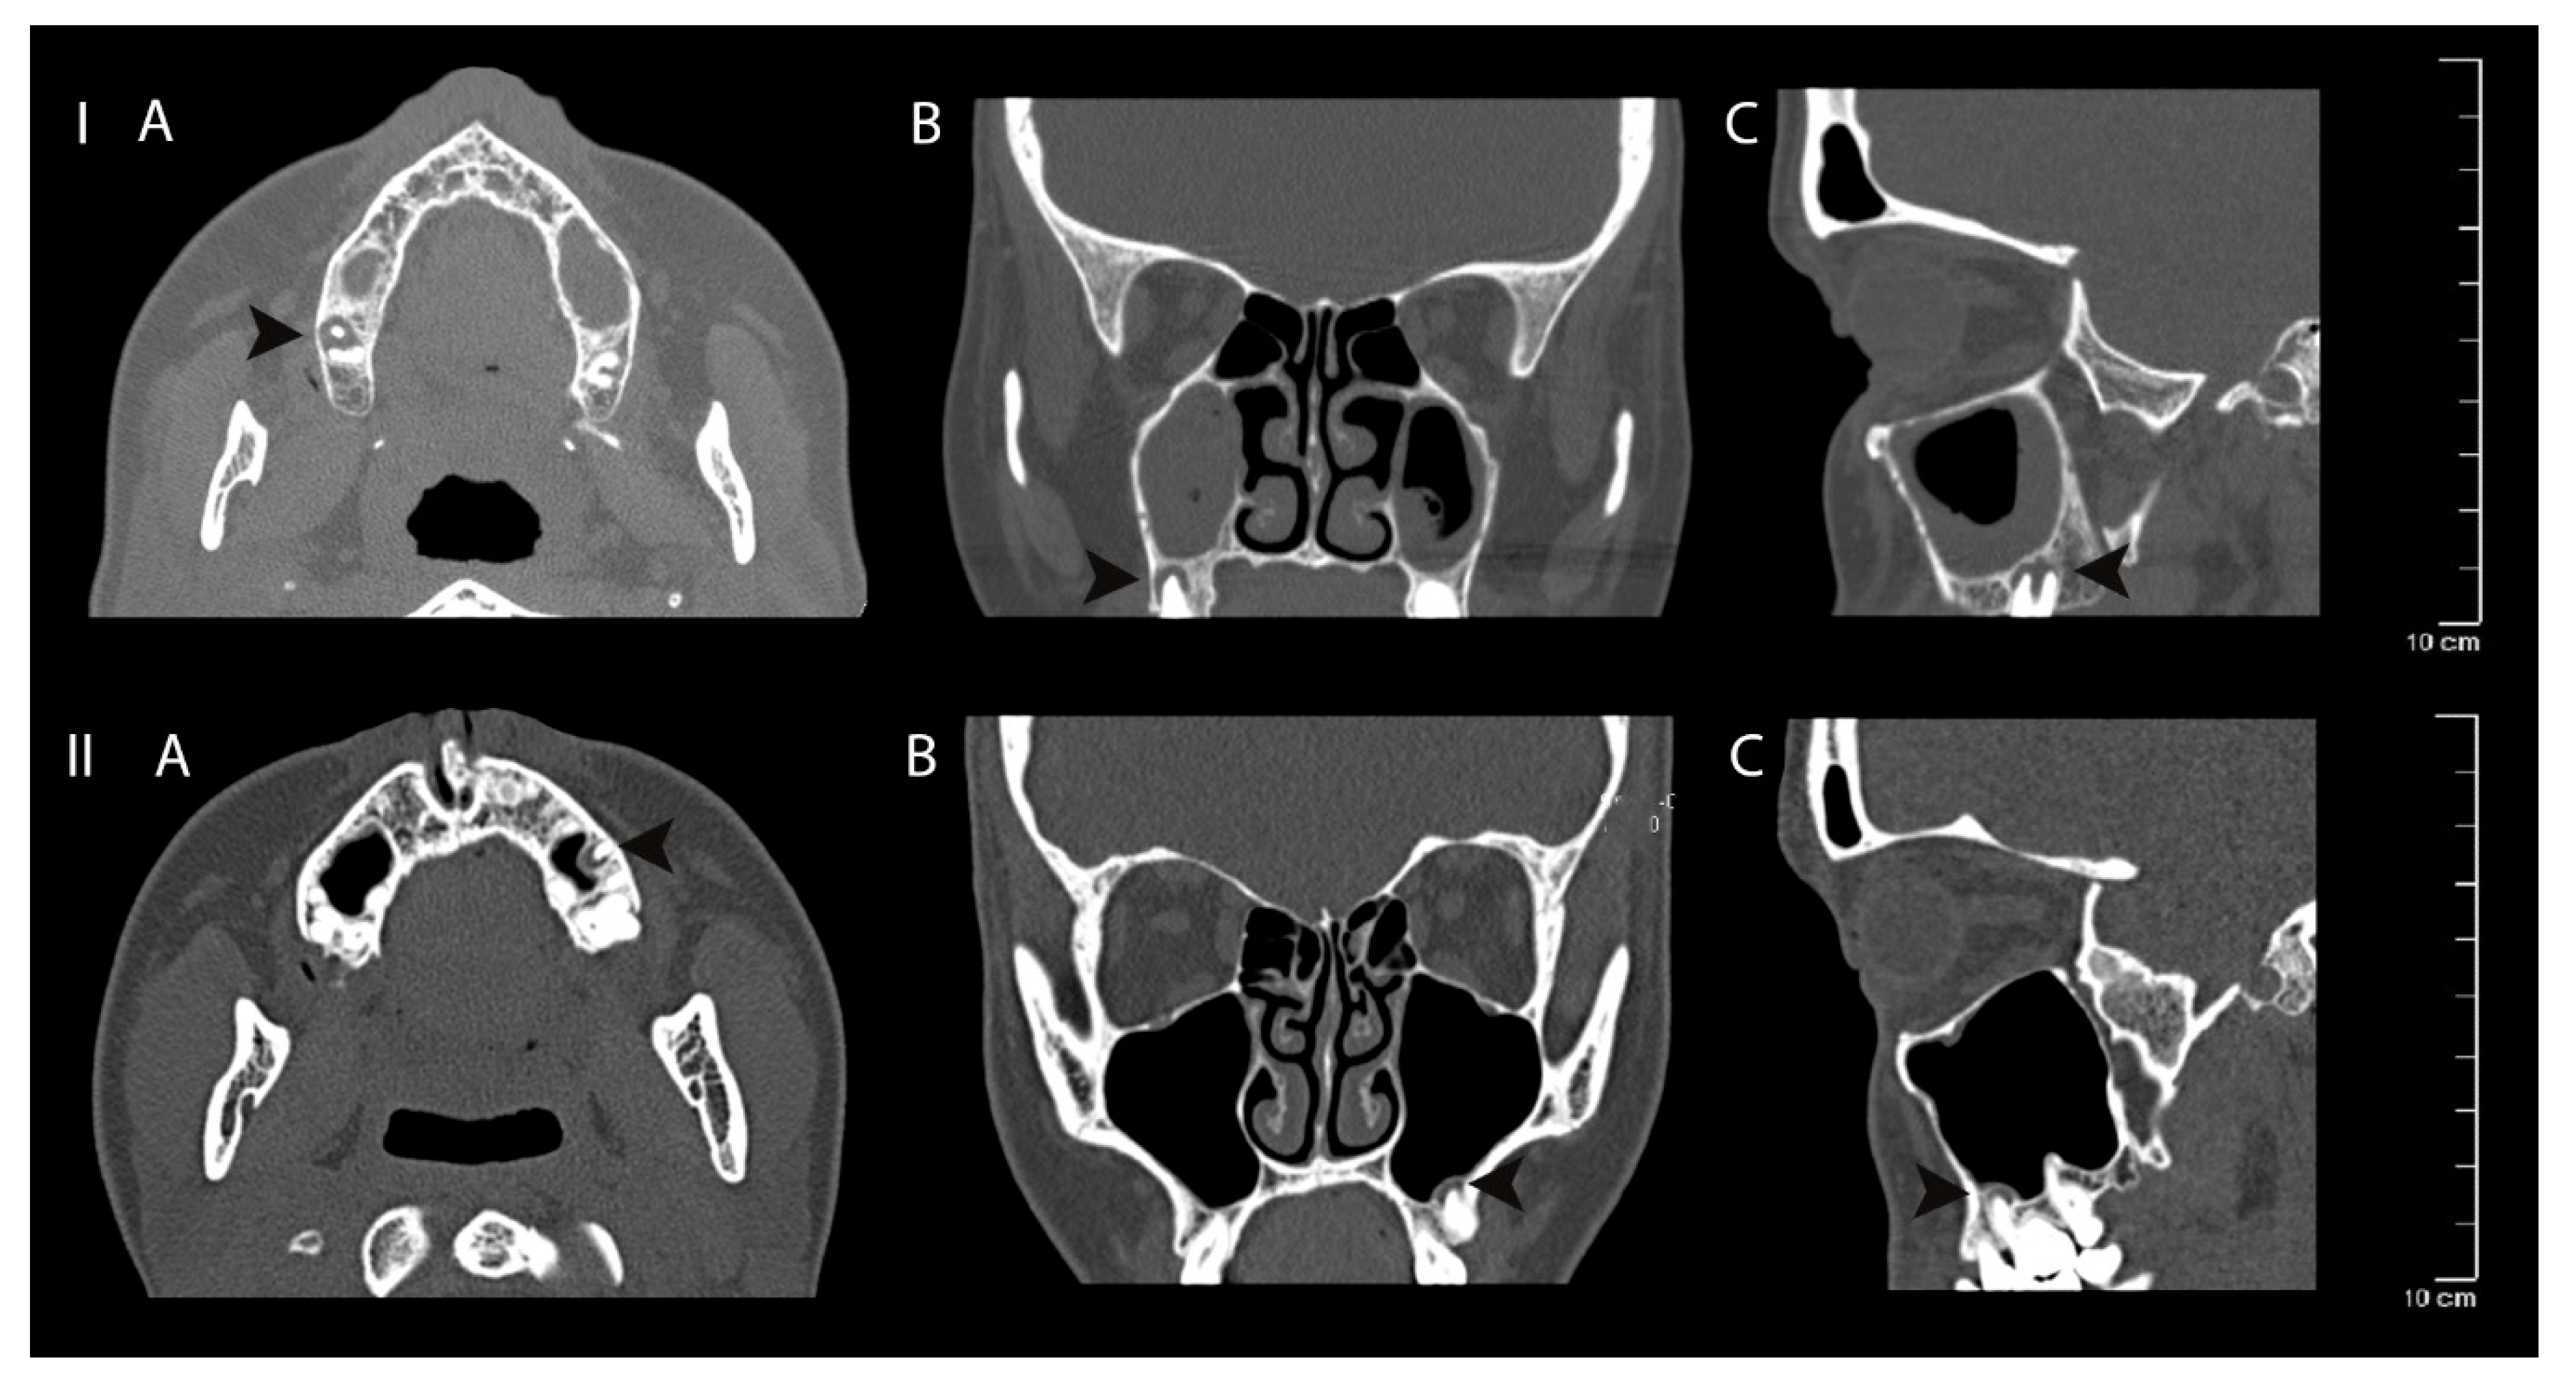

Figure 5.

Clinical case I—mucosal thickening—advanced, periapical bone destruction size S3; Clinical case II—mucosal thickening up to 2 mm, periapical bone destruction size S3. Computed tomography axial (A), coronal (B) and sagittal (C) views of apical periodontitis around the roots of the teeth and maxillary sinus mucosa thickening. The lesions are indicated with black arrows.